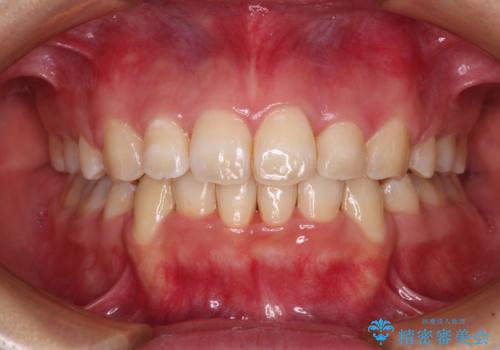

インビザラインによる矯正治療は、どれだけマウスピースを外す時間を短くできるかが成功の鍵となりますが、抜歯矯正ではよりシビアに要求されます。

こちらの患者様は、1日22時間以上を厳守してくださり、3年強で終えることができました。